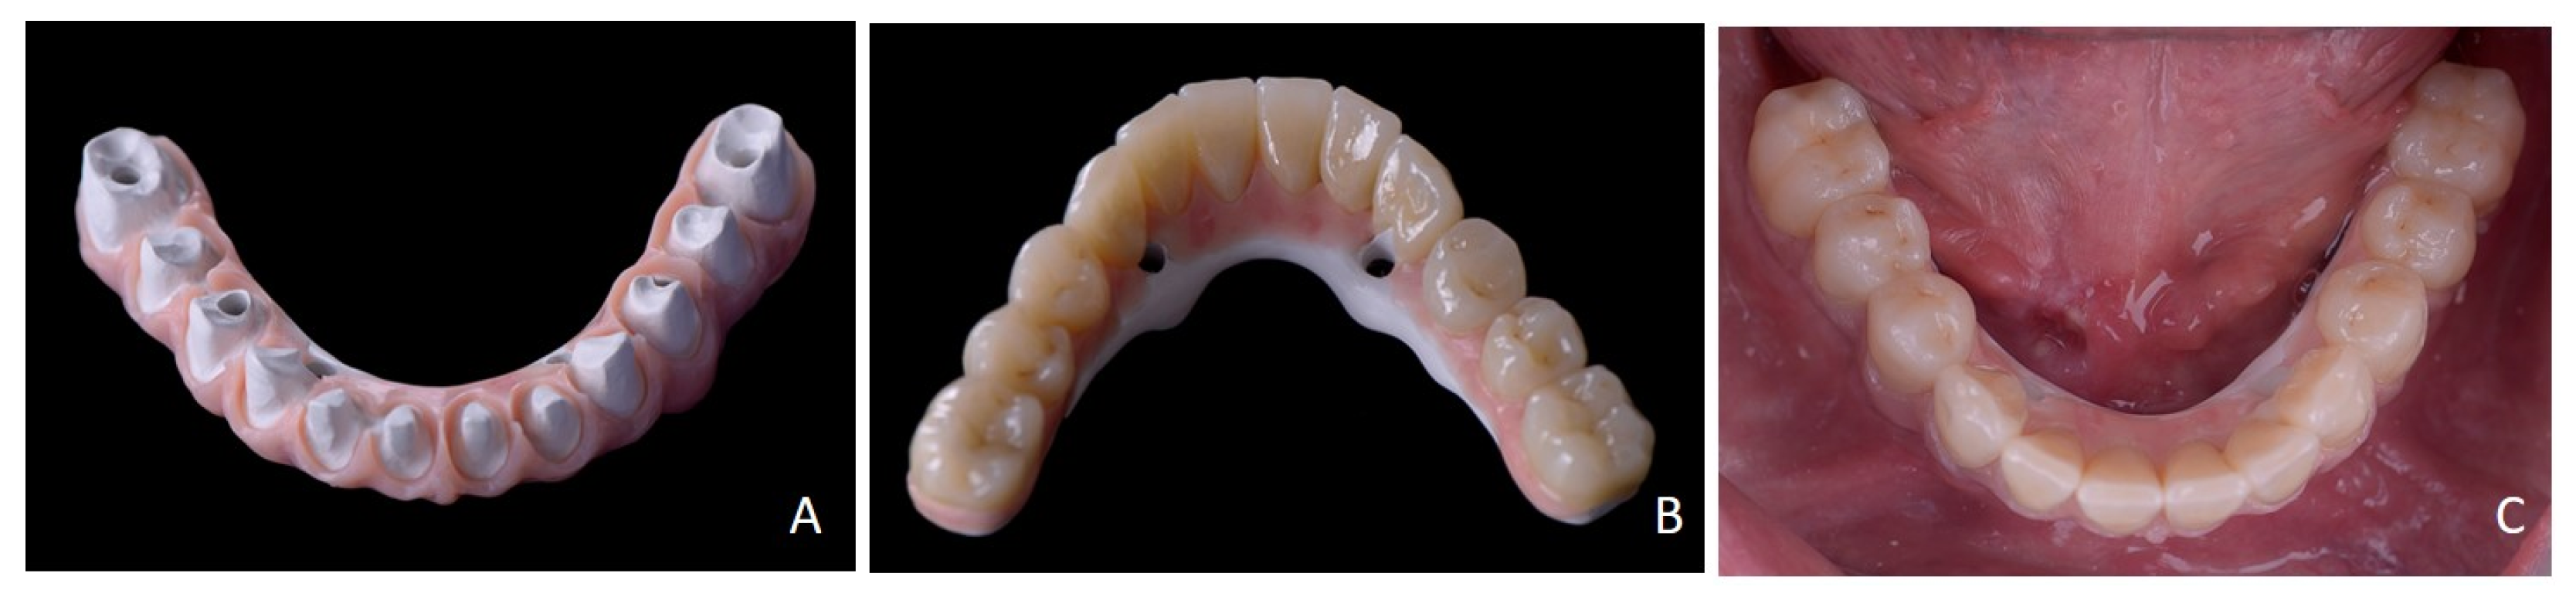

2. Case Report

3. Surgical Strategy

4. Discussion